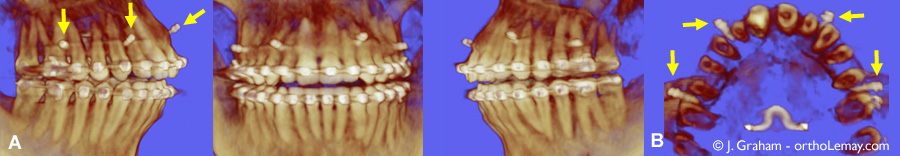

Images provenant d’une tomodensitométrie volumique à faisceau conique (TVFC) montrant la position des mini-vis d’ancrage indiquées par les flèches (A) Vues du côté droit, centre et gauche. (B) Vue occlusale montrant les mini-vis positionnées entre les racines.